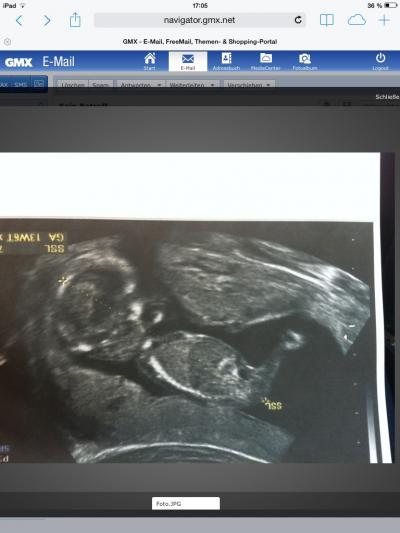

Hallo Mädls, ich bin überglücklich unseren Zwerg gehts bestens! Es hat während der Untersuchung Fruchtwasser getrunken :-) uns gewunken. Sich selbst gestreichelt. War ein wunderschöner Moment! Sooo süß einfach bin sooo happy!!!! Erstes Outing aber nicht sicher es wird ein Junge :-) in 5 Wochen dann den nächsten Termin. Hab gestern das erste mal ein flattern gespürt ... :-) könnte aber auch der Darm gewesen sein aber vl. Doch :-) Aber nicht mehr lange und man spürt es richtig, kann es nicht mehr erwarten!

Bild zu Baby gehts gut - Forum für April - Mamis